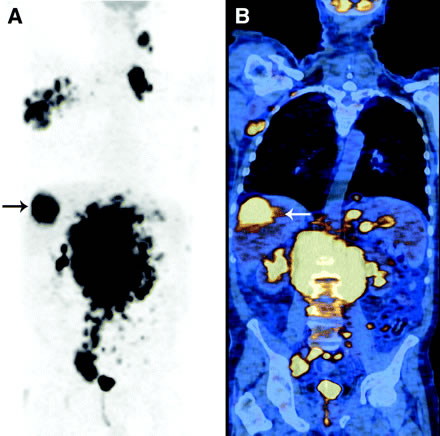

PET Scan went good on Wednesday afternoon. Shannon had more lab work and an office visit with the NP on Thursday morning. There was no results from the PET Scan at that visit. Blood work was still looking good, white blood cells were creeping back down to normal. Every other lab test was within normal range. The NP called Shannon on Thurday afternoon and said the PET Scan results were back and it showed “huge improvement” in her lymph nodes. Many of the lymph nodes had completely resolved and the others were reduced by 50% or so. The PET Scan measures in a value called “SUV” (Standardized Uptake Value). It shows areas where sugar metabolism is higher than surrounding tissues. The cancerous areas have higher sugar metablolism and show up as bright/brighter spots on the PET Scan. Other things can cause bright spots such as infection or inflammation as well. The doctors can compare her previous PET Scan images to help measure the progress we’re making. (Image attached is just a random PET Scan image from the internet….not Shannon’s).